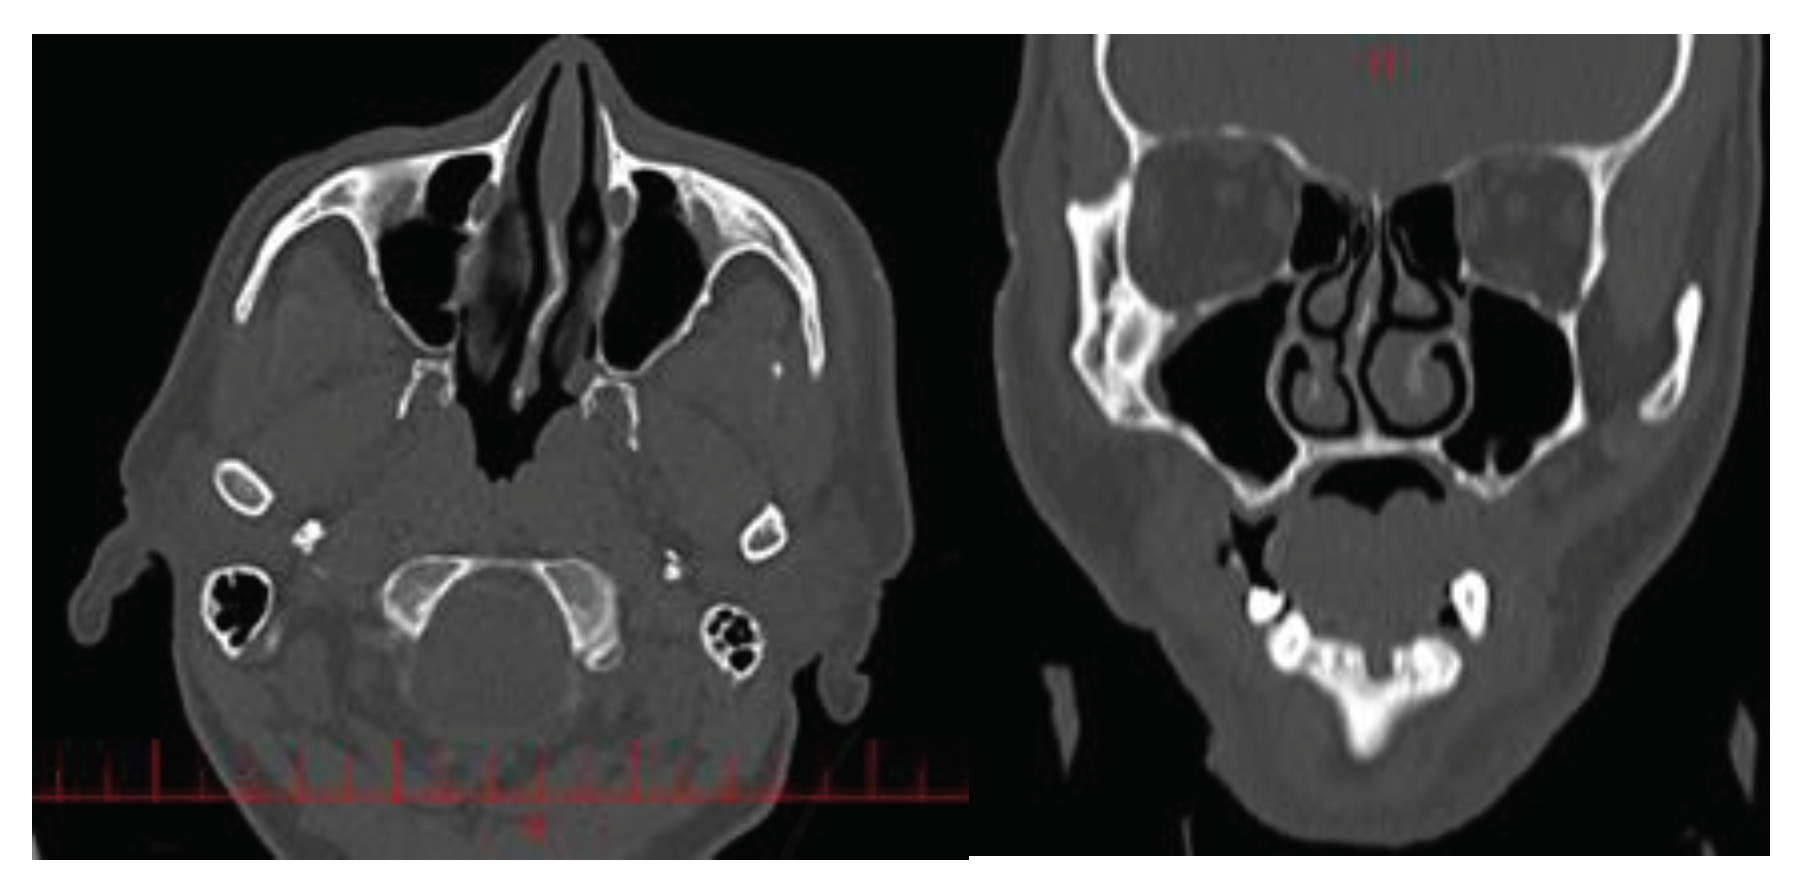

2.1. Geometry reconstruction: